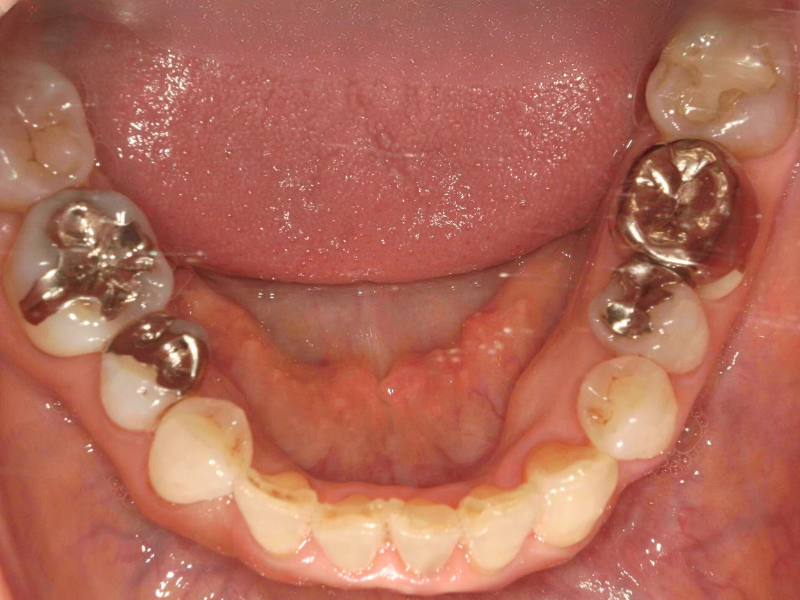

20代、男性、ワイヤー

| 施術内容 | 主訴:でこぼこで食べ物がよく挟まる。虫歯や歯肉炎に悩まされてきた。 詳細:ワイヤー矯正での歯並び改善 とても磨きやすくなったと満足されてます。 |

| 治療期間 | 16ヶ月(2/3現在 治療終了) |

| 費用 | ワイヤー矯正 60万円(税込660,000円) |